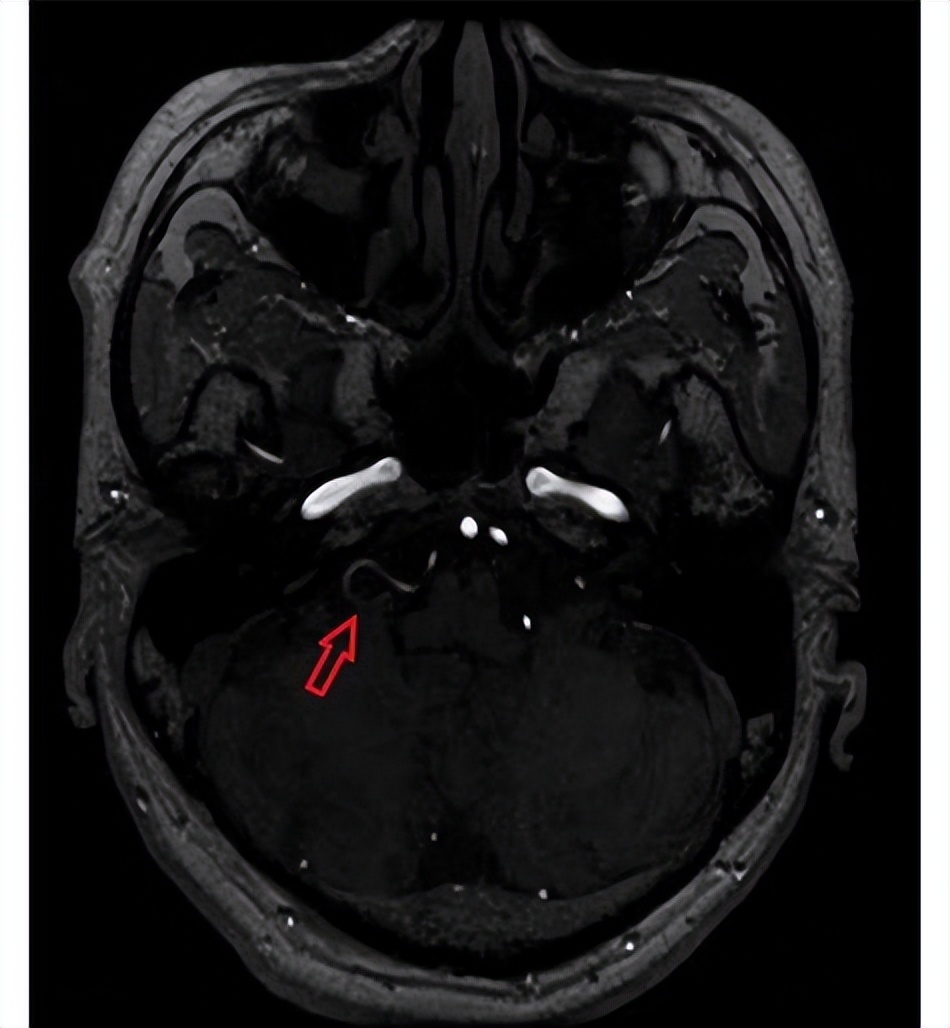

“门诊了解到他在做吞咽等动作时疼痛发作,且发生在单侧区域,是典型的神经痛表现。 ”王峰主任医师介绍,为进一步诊断,老金接受了磁共振神经血管成像检查,最终发现他右侧小脑后下动脉压迫舌咽神经。

术前磁共振

舌咽神经是人脑中一对颅神经,控制咽喉部肌肉的运动。与我们熟知的三叉神经痛一样,当舌咽神经受到血管压迫、肿瘤压迫、外伤刺激等因素影响时,也可能出现舌咽神经痛。而老金没有肿瘤、外伤等因素,医生考虑还是血管结构导致的血管压迫。